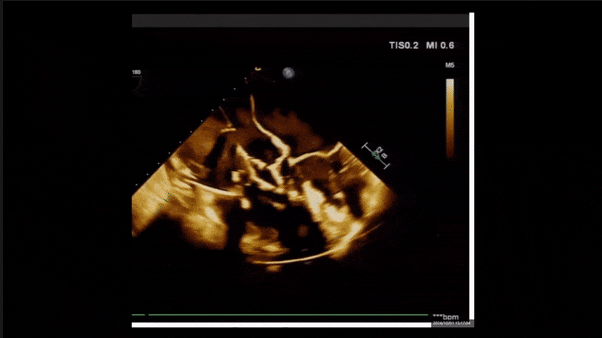

術(shù)后即刻返流

術(shù)后即刻返流三維

術(shù)后即刻經(jīng)食道超聲可見,三尖瓣假體瓣膜位置合適,牛心包瓣葉運(yùn)動狀態(tài)良好,開閉正常,瓣周及瓣葉對合緣處未見明顯返流,心電圖及心包狀態(tài)較術(shù)前無明顯變化。

術(shù)前術(shù)后返流情況對比